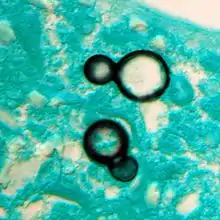

Large, broadly-based budding yeast cells characteristic of Blastomyces dermatitidis in a GMS-stained biopsy section from a human leg.

Once suspected, the diagnosis of blastomycosis can usually be confirmed by demonstration of the characteristic broad based budding organisms in sputum or tissues by KOH prep, cytology, or histology.[27] Tissue biopsy of skin or other organs may be required in order to diagnose extra-pulmonary disease. Blastomycosis is histologically associated with granulomatous nodules.